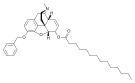

Codeine-dionine family

- Myrophine

Myrophine Myrophine |